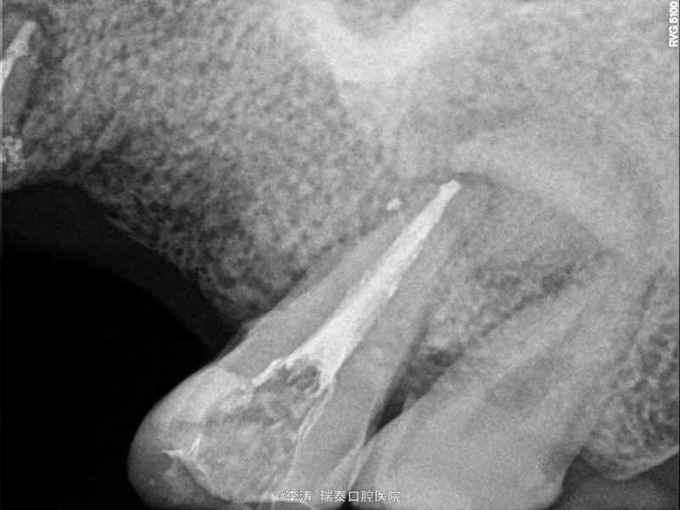

牙骨质瘤 牙骨质瘤

26残冠 25,27根管治疗不到位 27牙根尖区高密度影 所有牙均无临床症状

经多方会诊,确认考虑27牙根尖牙骨质瘤,建议先行根管治疗,然后密切观察 予以拔除26,根管治疗25,27